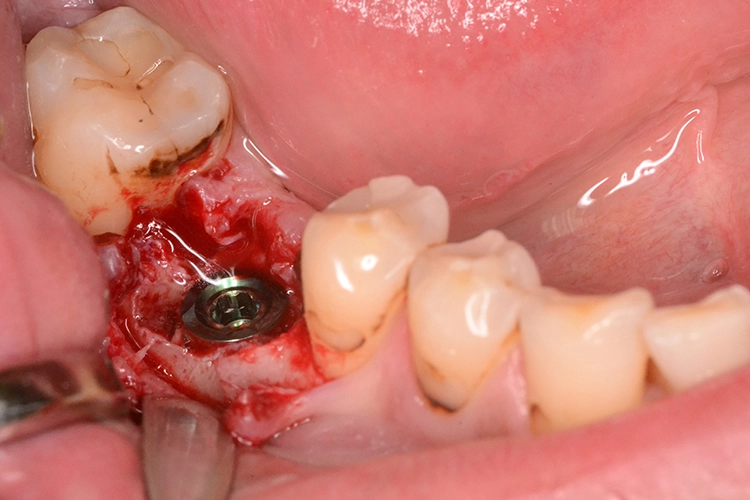

4. Sofortimplantation im Molarengebiet

Dr. Opitz

Aufgrund der Augmentation erfolgte die Freilegung 5 Monate postoperativ. Nach Ausformung des Emergenzprofils (Abb. 4i) erfolgte die definitive prothetische Versorgung durch eine okklusal verschraubte Einzelkrone (Abb. 4j).